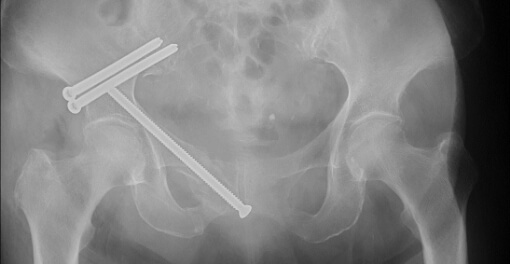

脆弱性骨盤骨折症例

転倒にて受傷した高齢女性。骨折部の転位が大きく疼痛も強かったため手術を行いました。手術は全身への負担が少ない低侵襲手術(小切開によるスクリュー固定)を行い、術後はすぐに荷重歩行訓練を開始しました。